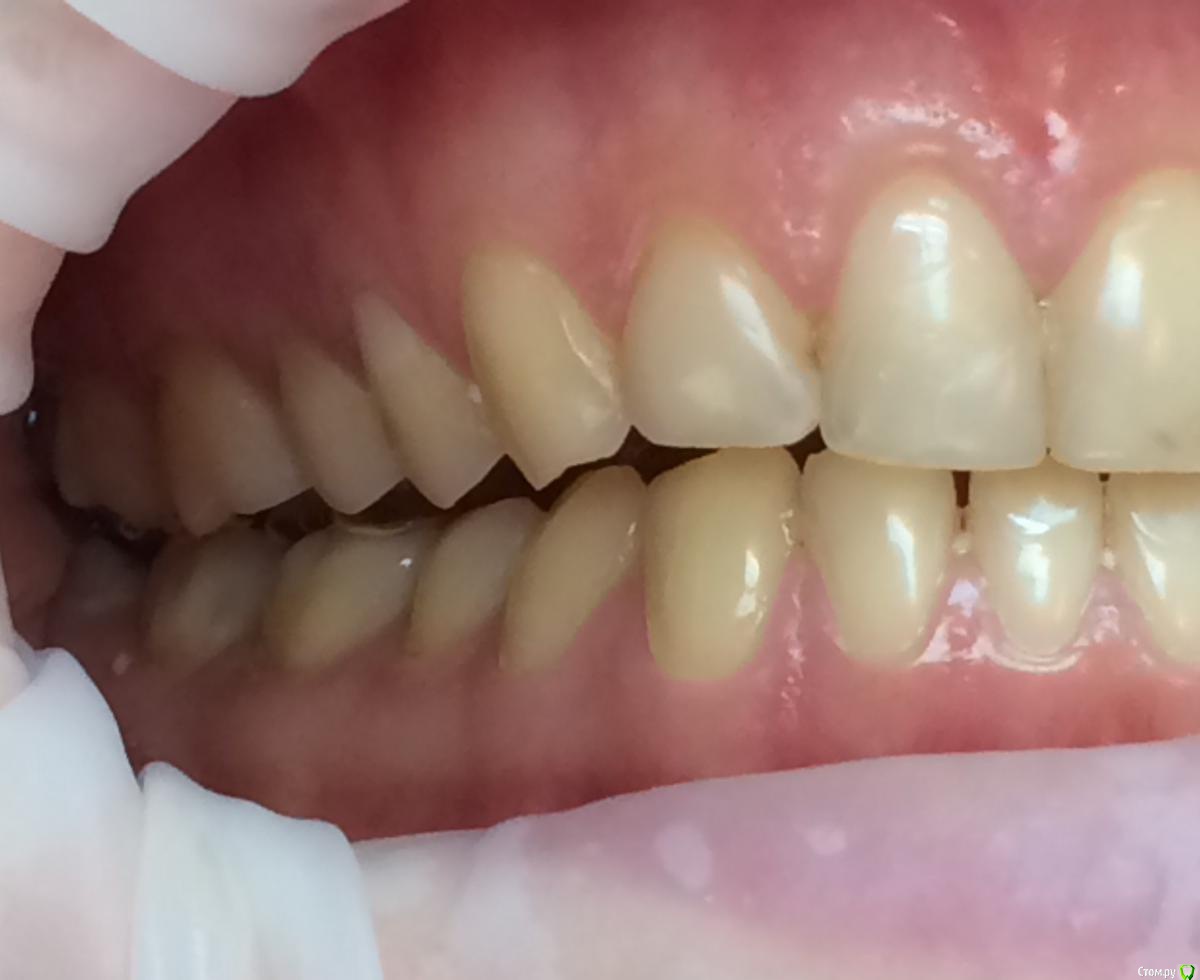

Larnary Опубликовано 28 июля, 2015 Поделиться Опубликовано 28 июля, 2015 (изменено) Добрый день!Ко мне обратилась пациент 1988 гр с жалобой на стираемость зубов и постоянные сколы пломб.Объективно небная поверхность верхних резцов стерта до дентина. Окклюзионная стираемость жевательной группы зубов.Прошу помочь с выявлением причины такой стираемости зубов и оптимальноно метода лечения Изменено 28 июля, 2015 пользователем Larnary Ссылка на комментарий

Larnary Опубликовано 28 июля, 2015 Автор Поделиться Опубликовано 28 июля, 2015 (изменено) Видно окклюзионнык интерференции в области 37 и 47.На днях удален 38 и дальше будут удалены остальные восьмерки. На ТРГ мне видится небольшая ретрузия верхних резцов,дистальный прикус. Так же левпя окклюзионная кривая более выраженная,чем правая Изменено 28 июля, 2015 пользователем Larnary 1 Ссылка на комментарий

Bobby Опубликовано 29 июля, 2015 Поделиться Опубликовано 29 июля, 2015 Фасетки стираемости на нёбных поверхностях верхних резцов и вестибулярных поверхностях нижних резцов обусловлены малым оверджетом - недостаточная щель по саггитали, поэтому и будут колоться реставрации, а ткани зубов истираться. Фрадеани про это на своём курсе рассказывал и показывал видео как это диагносцировать и что с этим делать. Что вообще хочет пациентка и на что готова? Эти вопросы лучше сразу решать на первичной консультации, а то делаете диагностики, всё рассчитываете, распинаетесь, а они потом: "ой, я пока не готов/а к такому плану лечения" и всё заканчивается композитной мазнёй в другой клинике. 5 Ссылка на комментарий